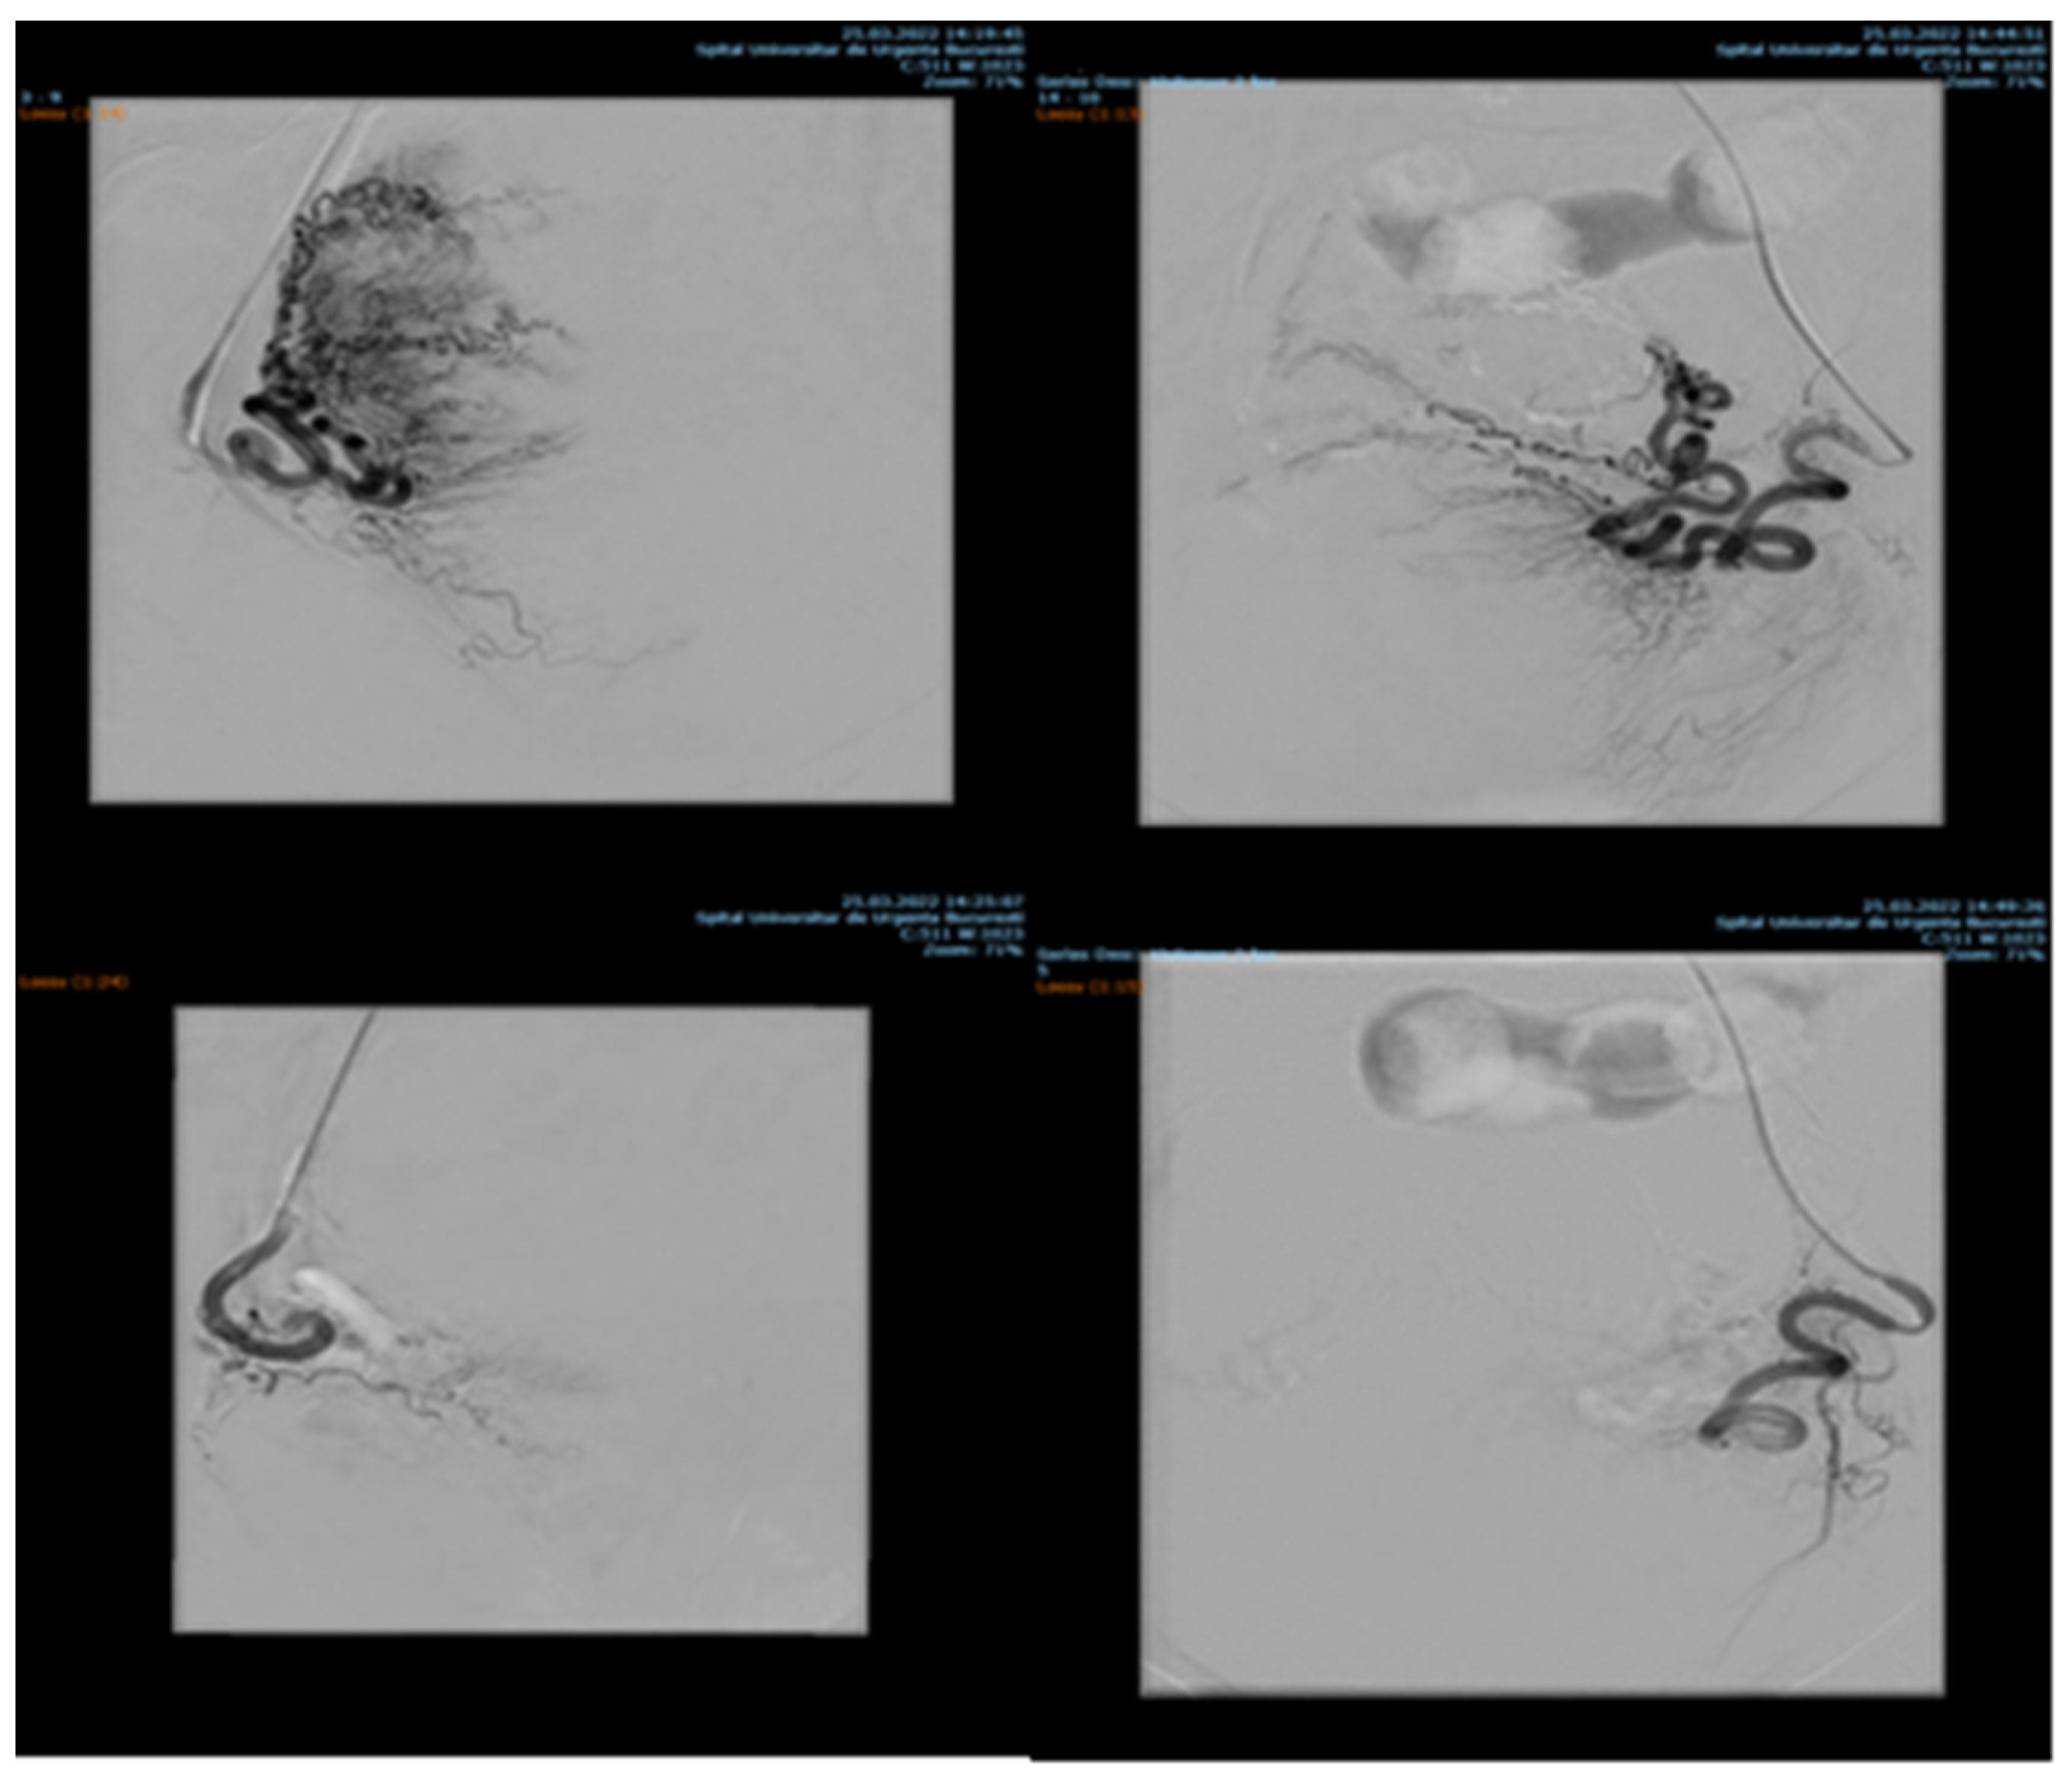

Endovascular procedures were used in 2.29% of cases with ectopic pregnancy (n = 26) (see Figure 4 and Figure 5), 1.23% of patients with arteriovenous malformation (n = 14) (see Figure 6), and 0.52% of patients with major hemorrhage of obstetrical causes (n = 6).

Figure 5. Pelvic artery embolization for C-scar ectopic pregnancy.